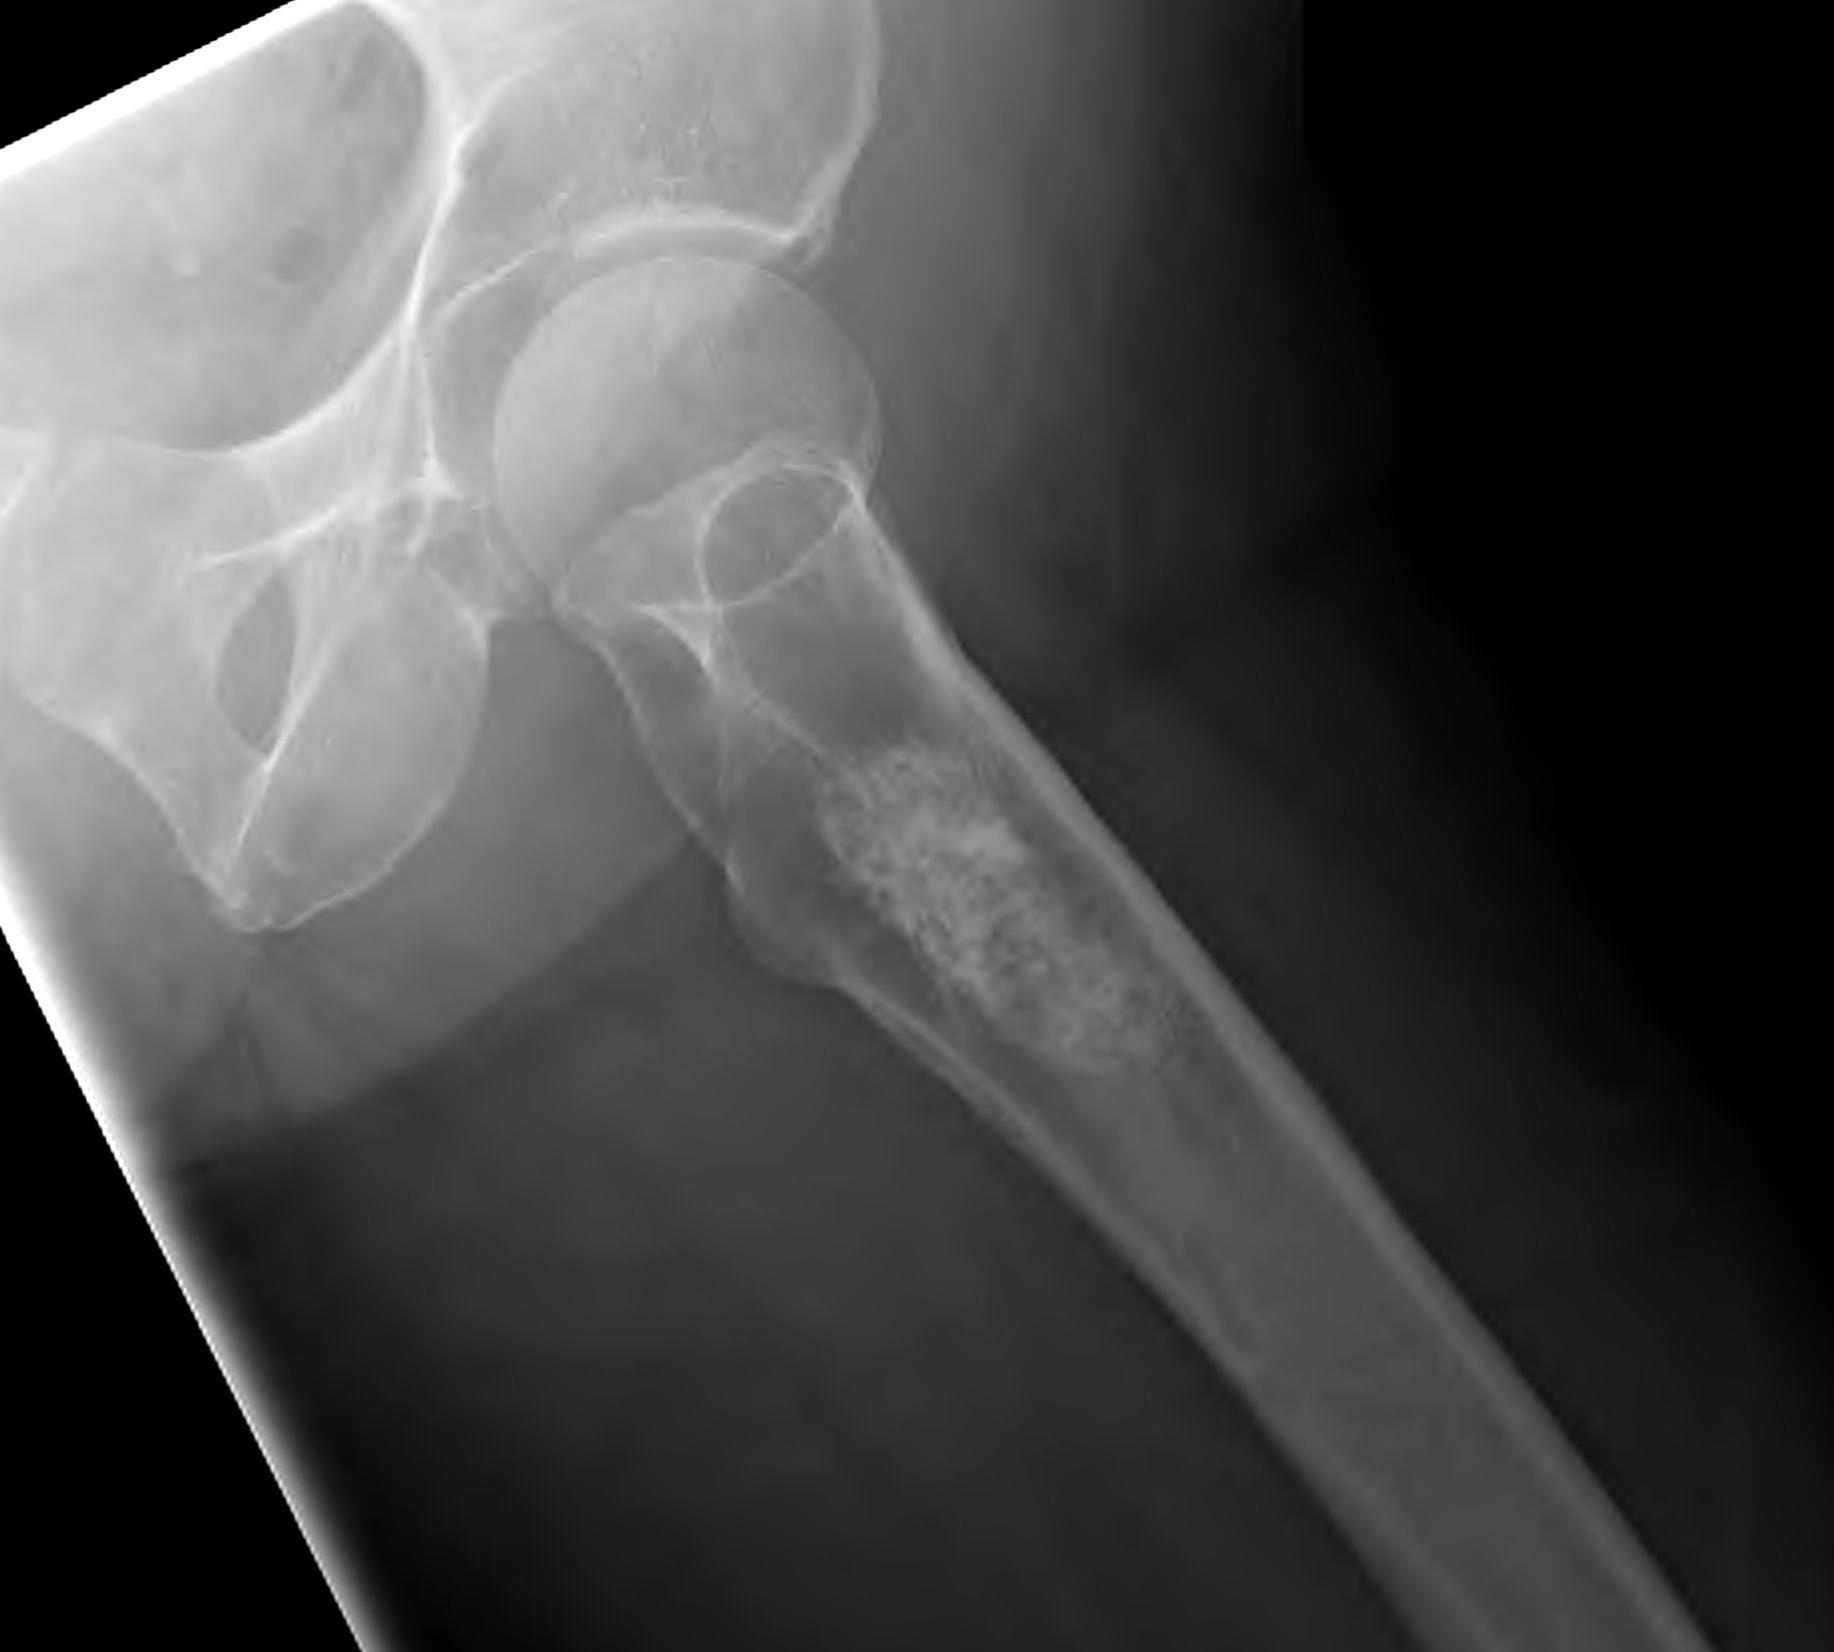

X-ray

Lytic lesion with punctate or spotty calcification

Worrisome features

- growth over time

- large > 5cm

- endosteal scalloping is hallmark of chondrosarcoma

Large calcified lesion with endosteal scalloping

Pathological fracture